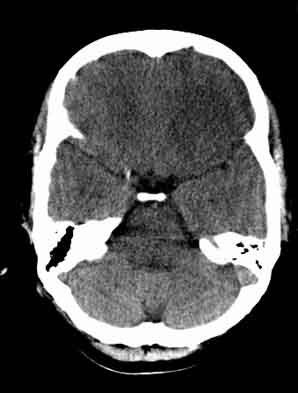

患者,女,29,头痛呕吐2月余,已建议增强或mri进检。

脑沟裂消失,脑白质密度似有减低,考虑脑炎。

大脑表面脑沟裂消失,颅压高的表现,经常遇到这样的现象,都没有一个明确的结论,望高人指点。

脑沟裂消失,脑白质密度似有减低,考虑脑炎。期待结果验证。

双侧脑室前角、旁周围白质低密度减低,边界模糊不清,患者女性:大胆推测,脑白质脱髓鞘改变。mri检查